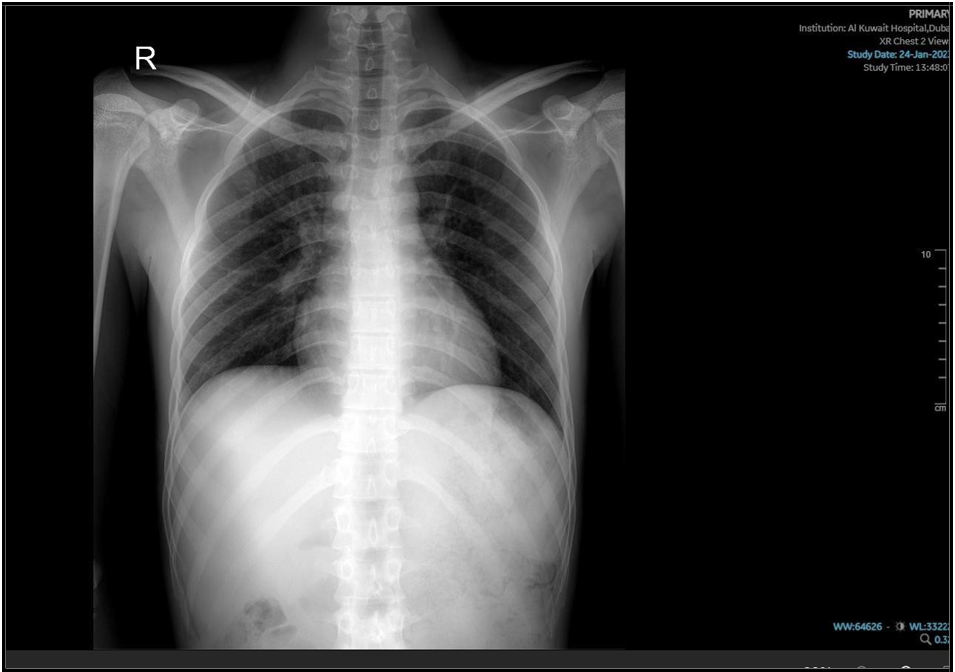

He started with the intensive phase of 4 medications for the 6 months anti tuberculous regime; his cough had improved, as well as follow- up lab test of CBC, electrolytes-renal functions and LFT were all normal, while CRP dropped to 8.7 and ESR to 10. The repeated chest x-ray, performed 2 weeks after initiating therapy, demonstrated mild improvement of the initial findings. The Mycobacterial culture confirmed sensitivity to both Rifampicin and Isoniazid, which supports the continued use of the standard first-line anti-TB regimen.

(“05 Dec. 2024”) Slight improvement of the opacity is seen

After three weeks on the four-drug anti- tuberculous regimen, the patient deteriorated, initially presenting with a mild, itchy maculopapular rash, followed by the onset of nausea and pyrexia. He was treated symptomatically, and pyrazinamide was discontinued as it was suspected to be the cause of the rash. Although his initial symptoms began to improve following the discontinuation of pyrazinamide, within a few days the patient deteriorated further— developing shortness of breath, elevated inflammatory markers (CRP increased to 87 mg/L, Procalcitonin to 0.6 ng/mL), and a one-fold elevation in transaminase liver enzymes. A requested sputum culture failed to identify any superadded bacterial or fungal pathogens. High- resolution CT chest done and showed a progressive course.

(“29 Dec. 2024”) CT showed Focal patchy consolidative opacity noted in right upper lobe with multiple poorly defined linear and reticulo- nodular opacities in bilateral lower lobes.